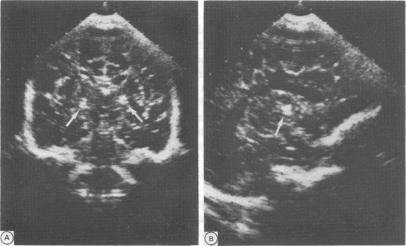

Clinical observations and findings on imaging are reported in six newborns with symmetrical thalamic lesions (STL). In three cases the diagnosis was confirmed by postmortem examination. Characteristic observations in this series and 17 previously reported cases include no evidence of perinatal asphyxia, high incidence of polyhydramnios, absent suck and swallow, absent primitive reflexes, appreciable spasticity at or within days of birth, lack of psychomotor development, and death within days or months. Characteristic pathological findings include loss of neurons, astrogliosis, and 'incrusted' neurons particularly in the thalamus. In two thirds of cases the basal ganglia and brain stem are involved as well. A hypoxic-ischaemic event occurring two to four weeks before birth is most likely responsible for STL. Bilateral thalamic calcification can often, but not always, be demonstrated in the newborn period by computed tomography and/or cranial ultrasound. The presence of these calcifications and the observation of spasticity at birth imply that the responsible insult occurred at least two to four weeks earlier. The small number of published cases with STL suggest that it may be easily missed.